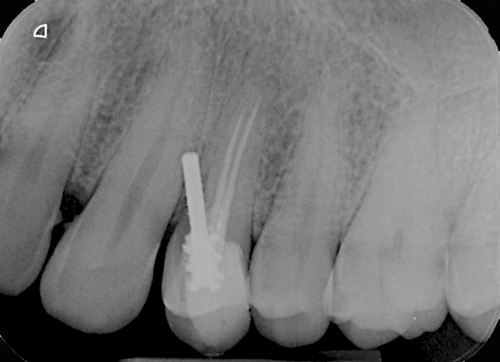

Furthermore, the reconstruction of endodontically treated teeth can present restorative and esthetic challenges for the technician and clinician.23 The failure of these post-retained systems has been documented in numerous clinical studies.10,13,21,24-29 Many of these studies indicate that the failure rate of restorations on pulpless teeth with posts and cores is higher than that for restorations of vital teeth because of their structural differences and the significant loss of tissue.30-35 Several main causes of failure of post-retained restorations have been identified, including recurrent caries, endodontic failure, periodontal disease, post dislodgment, cement failure, post-core separation, crown-core separation, loss of post retention, core fracture, loss of crown retention, post distortion, post fracture, tooth fracture, root perforation (Figure 1), improper post placement (Figure 2), and root fracture.11,36,37Also, corrosion of metal posts has been proposed as a cause of root fracture.38 A post and core system fabricated with dissimilar metals can cause galvanic corrosion that occurs between the two dissimilar materials.39 This gradual destructive process involves the electrical interaction of at least two different metals or nonmetallic conductors in an environment (ie, microleakage) that accelerates the corrosion of at least one of them, while the least noble metal corrodes the most.

Fig 2. Improper metal post placement/perforation (dentistry courtesy of Riccardo Tonini, MD, DDS).

Figure 2